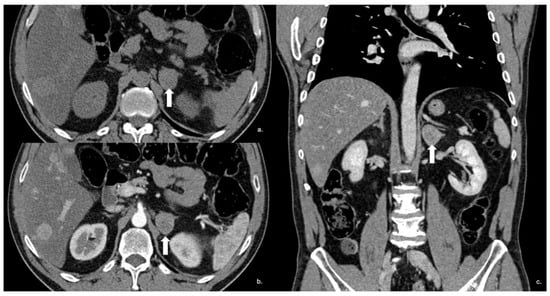

Figure 4.

36-year-old man with history of night sweats, hypertension, and tachycardia due to pheochromocytoma (arrow). Non-contrast CT shows an inhomogeneous right adrenal mass > 20 HU (A). In the arterial phase (B), the mass shows intense enhancement of the solid components with persistent enhancement. In the late phase (C), absolute contrast medium washout is <50%.